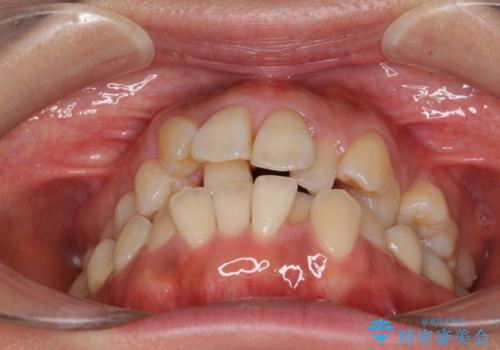

- 上顎の著しい叢生と奥歯の咬みにくさを気にして来院された患者様です。

骨格的に上顎は狭く、下顎は右側にシフトしていたため、右側臼歯はクロスバイトとなっていました。

上顎骨を急速拡大装置により拡大し、ワイヤー装置による抜歯矯正治療を行うこととしました。